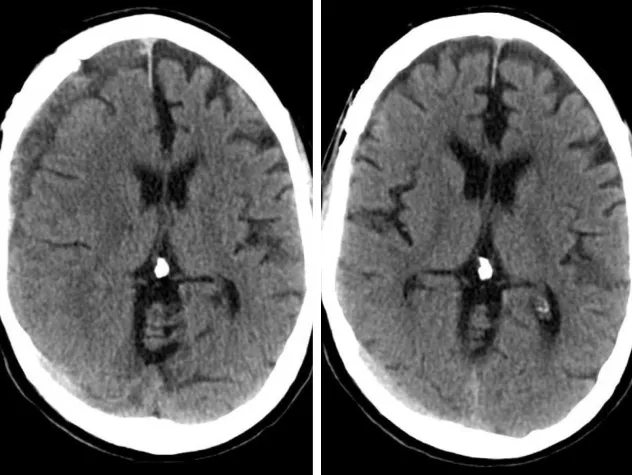

Innovative technologies and alternatives to traditional treatments are transforming the diagnosis and management of neurological conditions. In 2025, NewYork-Presbyterian physicians and surgeons from Columbia and Weill Cornell Medicine used sonication and convection-enhanced delivery to penetrate the blood-brain barrier, validated an adjunctive treatment for subdural hematoma, broadened access to spine surgery, advanced experimental therapies for neurodegenerative diseases, and more. Our specialists have been steadfast in reshaping the fields of neurology and neurosurgery in the pursuit of better patient outcomes and enhanced quality of care.

From cutting-edge research to compassionate patient practice, neurologists and neurosurgeons from Columbia and Weill Cornell Medicine are at the forefront of developing and applying the most advanced approaches to treat debilitating conditions affecting the brain and spine. With a broad range of focus on neurodegenerative and neurovascular disorders to malignant tumors, our innovative and advanced care is leading to new treatment options and enabling patients to achieve the best possible outcomes.